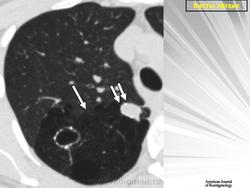

Воздушные кисты

Приложения:

1.vk_.slayd46.jpg